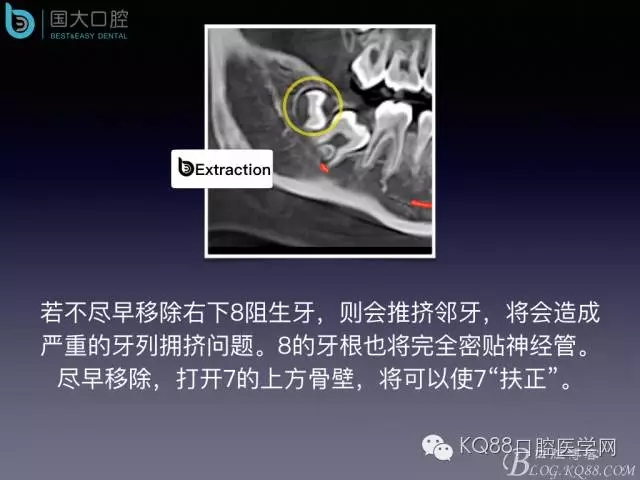

阻生牙的預(yù)防性拔除

- 牙齒拔除適應(yīng)證及第二磨牙遠中齲病